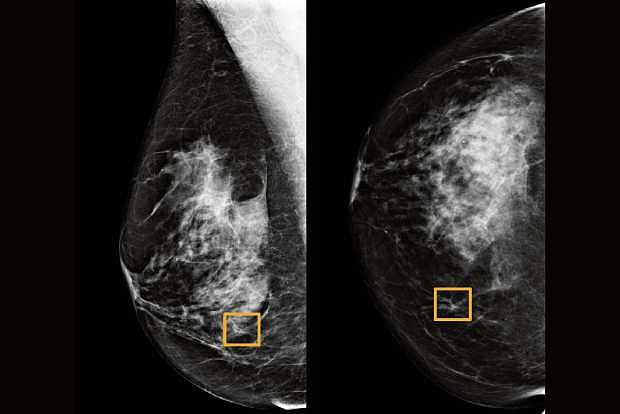

Study finds Google system could improve breast cancer detection

A Google artificial intelligence system proved as good as expert radiologists at detecting which women had breast cancer based on screening mammograms and showed promise at reducing errors, researchers in the United States and Britain reported.

The study showed the AI system could identify cancers with a similar degree of accuracy to expert radiologists, while reducing the number of false positive results by 5.7% in the U.S.-based group and by 1.2% in the British-based group.

It also cut the number of false negatives, where tests are wrongly classified as normal, by 9.4% in the U.S. group, and by 2.7% in the British group.